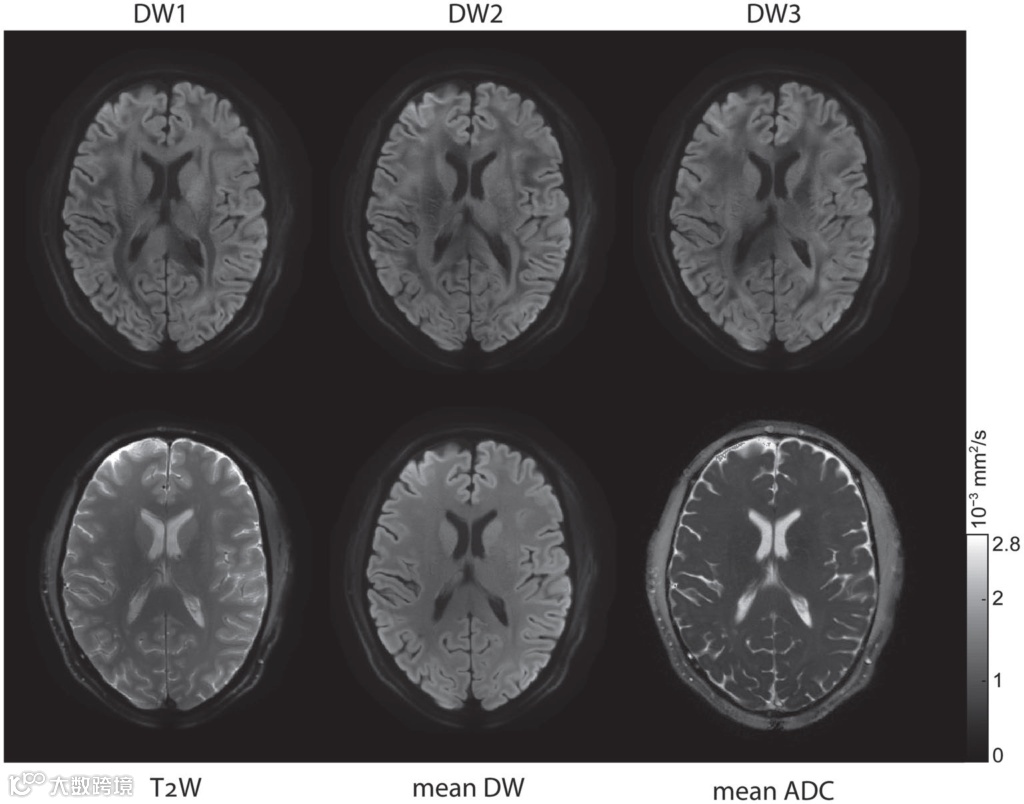

扩散加权成像(上排)和b=0、平均DWI和平均ADC(下排)

Adapted from Wilm et al. (2020)

选用恰当的方法解释额外相位便可利用测量数据重建出高质量的扩散影像。